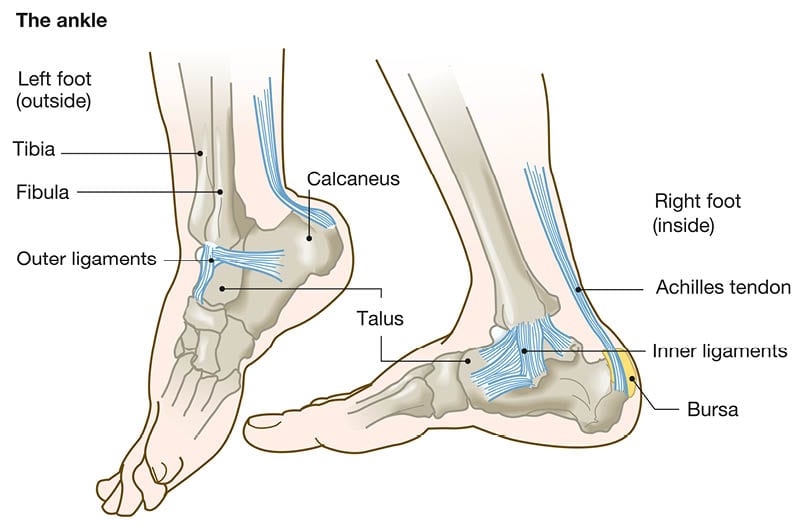

Anatomy of the Ankle

The ankle is a complex joint, made up of bones, tendons, and ligaments, which are the tough bands of tissue that run along the inside and outside of your ankle that hold the bones together. They help to stabilize the joint. An ankle sprain occurs when you stretch or tear these ligaments by forcing them into a position that is beyond the normal range.

Our feet tend to turn inward as we walk, so sprained ankles most commonly happen when the ankle rolls inward, resulting in lateral ankle sprains. These occur when you stretch or tear the ligaments on the outside of your ankle. Medial ankle sprains are less common. This is when you injure the ligaments on the inside of the ankle. A syndesmotic ankle sprain- or high ankle sprain- involves the tearing of the ligaments above the ankle. Though this type does not occur as often, it can be combined with lateral and medial sprains and often takes months to heal.